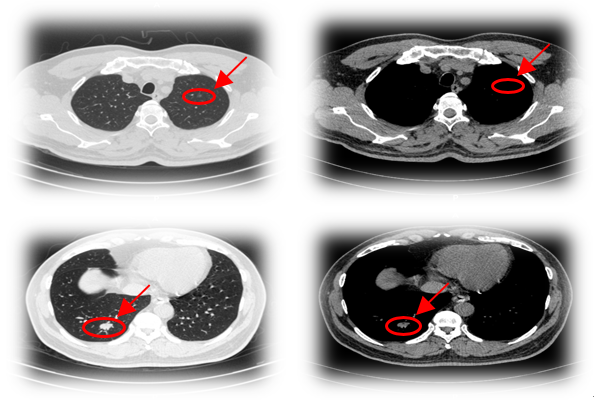

▲患者入院时胸部CT

治疗方案:

手术方式:

单孔胸腔镜下:肺癌根治术(右下肺叶切除+系统性淋巴结清扫)。术后3天顺利出院。

术后病理及分期:右下肺浸润性腺癌,pT1bN0M0, IA2期。

▲左上肺结节右肺术后1月行微波消融(MWA)治疗